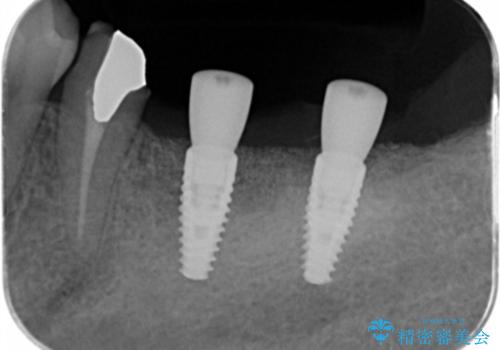

遊離歯肉移植術を併用した、破折歯のインプラント治療

- 他院で根の治療まで終え、違和感が取れず相談に来院されました。

当該歯を精査したところ、歯根に破折が見られ抜歯を余儀なくされました。

抜歯後、インプラントを用いて咬合機能を回復すると共に周囲に強固な角化歯肉を移植することによりより長期にわたり安定したインプラント周囲環境となるよう治療を計画します。

- 83.6万円(インプラント×2・アバットメント×2・クラウン×2)費用は治療当時の料金となります